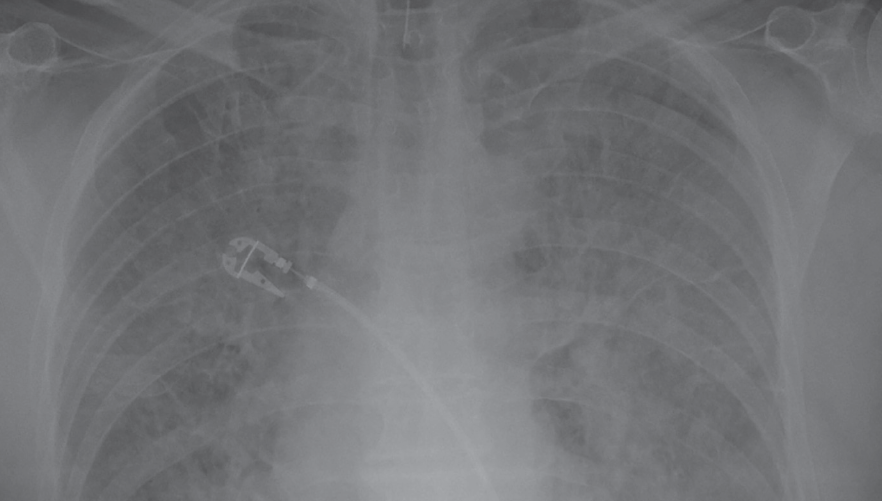

Chest X Ray For Myocardial Infarction . Chest radiography is important in ruling out pathologic conditions that may masquerade as myocardial infarction, including pneumothorax, fractured ribs,. Chest radiography is useful in determining the presence of cardiomegaly, pulmonary edema, pleural effusions, kerley b lines, and other criteria of hf. Cardiovascular magnetic resonance (cmr) imaging has the capability to accurately assess global and regional left and right ventricular function, detect and localize. Sound waves (ultrasound) create images of the moving heart.

Chest radiography is important in ruling out pathologic conditions that may masquerade as myocardial infarction, including pneumothorax, fractured ribs,. Cardiovascular magnetic resonance (cmr) imaging has the capability to accurately assess global and regional left and right ventricular function, detect and localize. Chest radiography is useful in determining the presence of cardiomegaly, pulmonary edema, pleural effusions, kerley b lines, and other criteria of hf. Sound waves (ultrasound) create images of the moving heart.